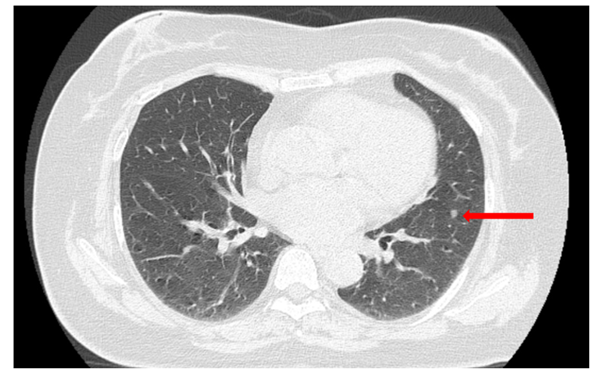

Cắt lớp vi tính (CT) lồng ngực (07/2024):

Hình ảnh thùy dưới phổi trái sát rãnh liên thùy có 02 nốt đặc, đường kính 4 mm và 4,5 mm, bờ tròn đều.